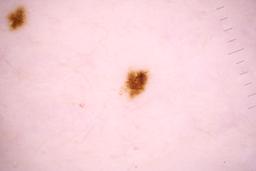

Evaluation set from the ML challenge: SIIM-ISIC Melanoma Classification.